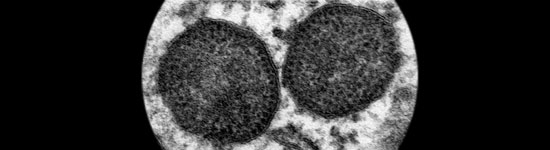

Novedades sobre las vías de excreción, rutas de transmisión, factores de riesgo, etc y la explicación de porqué PCV2 se convierte en un virus patógeno.

El PCV2 se ha ido asociando cada vez a más patologías, denominadas colectivamente enfermedades asociadas a PCV2 (PCVDs), como ES-PCV2, EP-PCV2, EE-PCV2, ER-PCV2, IS-PCV2 y SDNP.